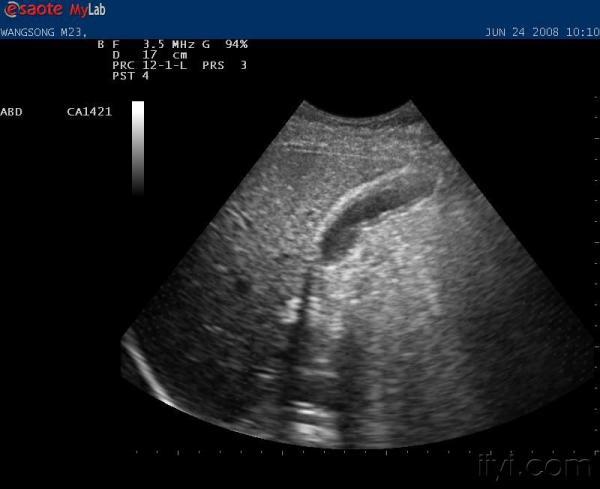

请大家帮助看看这个胆囊有没有问题

年轻男性,23岁,无任何不适症状,体检时发现.(禁食水检查)

超声所见:胆囊大小正常,胆囊壁厚,约4MM,且不光滑。

胆囊壁增厚,胆囊腺肌病?肝质地回声不均匀,是否得过肝炎

慢性胆囊炎